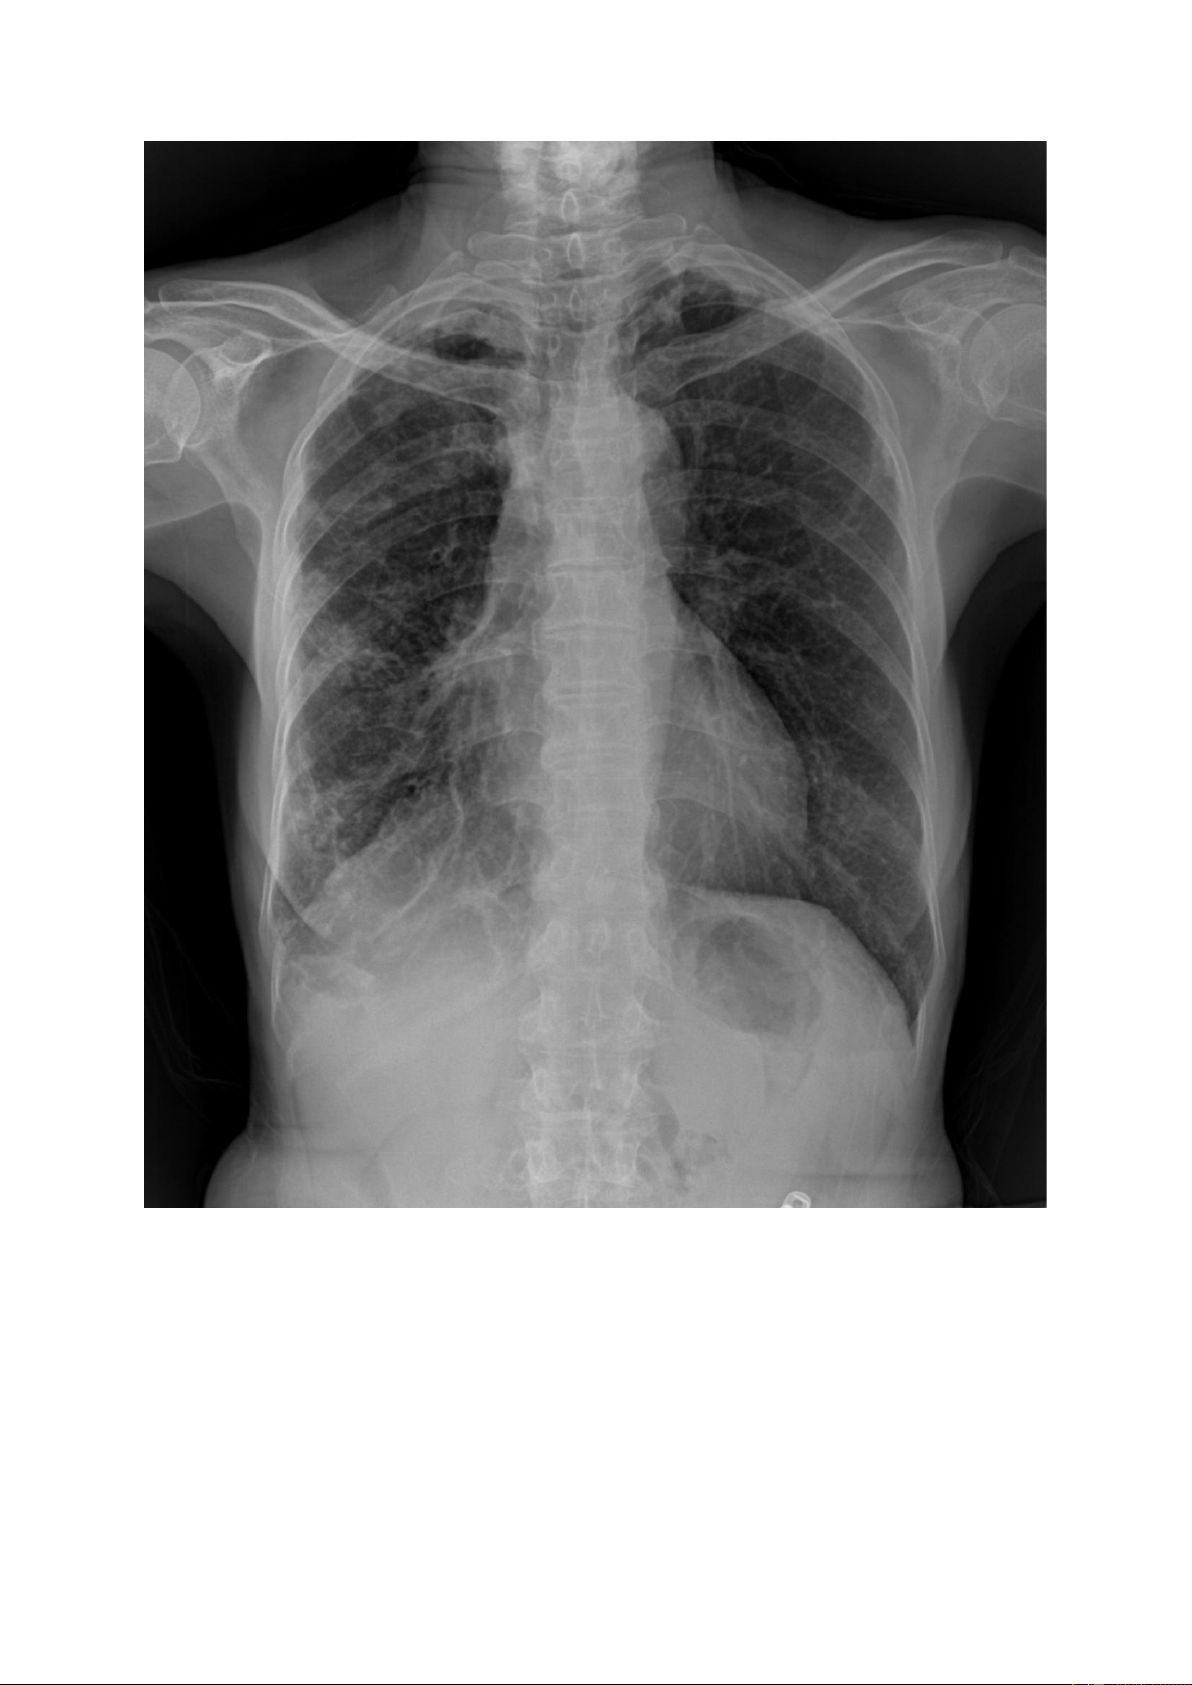

Nốt mờ lớn: là tổn thương có kích thước >3mm và < 3cm, số lượng có thể đơn

độc hoặc nhiều, kích thước có thể đều hoặc không đều, đậm độ cản quang khác nhau. lOMoAR cPSD| 22014077 lOMoAR cPSD| 22014077 1.3.